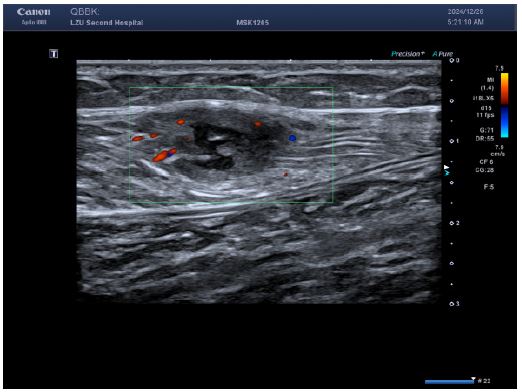

Imaging studies (Figures 1-4):

Lower limb ultrasound: Revealed multiple hypoechoic masses within the medial compartment of the right thigh and medial left calf musculature, suggestive of schwannoma; CEUS recommended.

Figure 1: Multiple echogenic areas were detected in the muscle layer of the left medial calf, all with regular morphology, clear borders, and heterogeneous internal echogenicity.

Figure 2: Color Doppler flow imaging showed a small amount of short rod-shaped blood flow around the lesion.